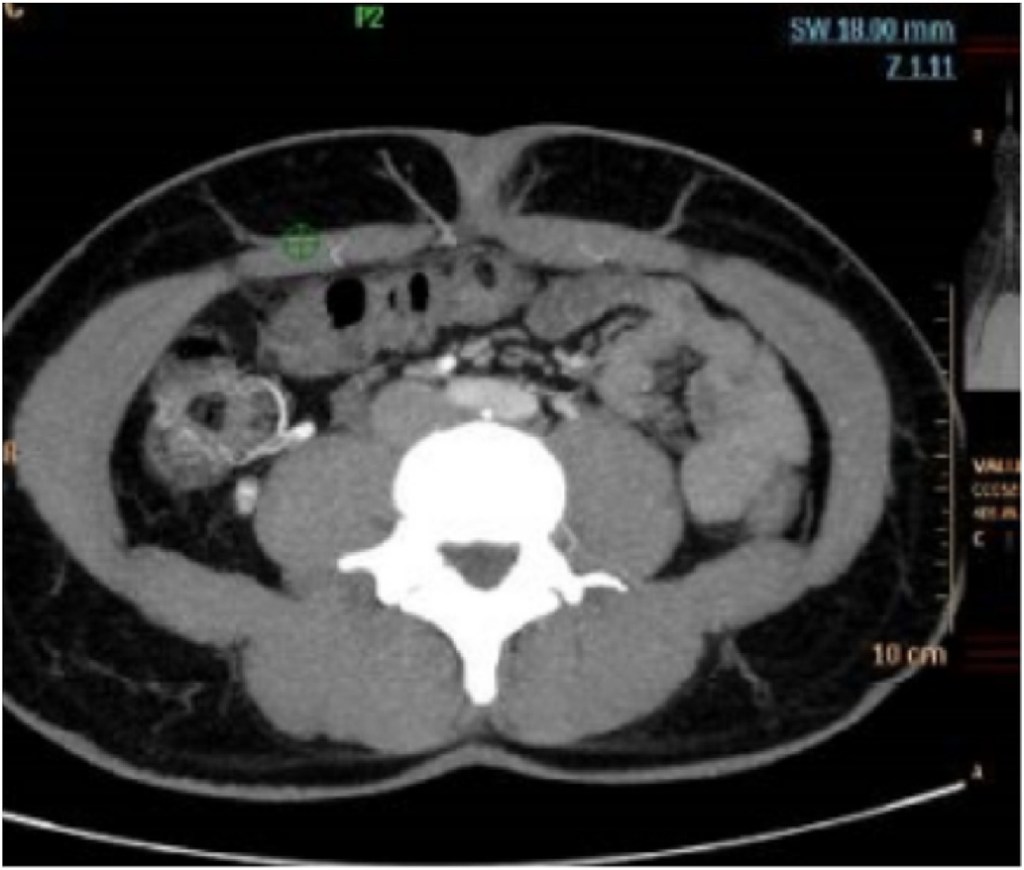

Angio CT and Angio MRI are more reproducible than DUS, and in both cases the perforators are identified by the imaging team and a “map” is drawn to help the surgeon in identifying the best vascular anatomy for the reconstruction. This process is time consuming and includes two phases: technician dependent – the slice reconstruction and the vessel identification; radiologist dependent – the manual identification of each of the contrast enhanced perforating branches of the epigastric, their location in the abdomen related to the umbilicus, calibre and direction after perforating the abdominal fascia (Fig. 1).

view).

An Angio CT was performed pre-operatively in the 40 included patients, using a CT Spectral Scanner with a 64-detector row (Philips Iqon), a 140 Kv tube voltage and a 120e160 mAs fixed tube current. Further settings included 0.75 rotation time, collimation of 128, pitch of 0.609 and a 512 Matrix. 80e100 ml of contrast was injected with images acquired in Bolus Tracking. Images started 5 cm above the umbilicus to the lesser trochanter (range of 32 cm) with a thickness of 0.8 mm and an increment of 0.4 mm.